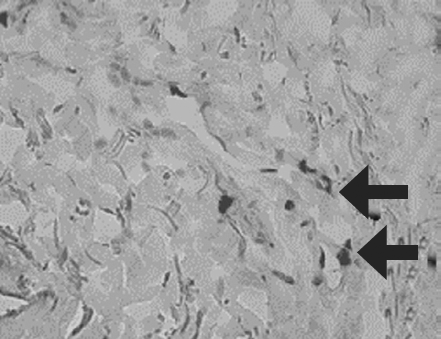

Histological examination of biopsy samples taken from the area of ATMSC transplantation for all the patients revealed the presence of pronounced vascularization with the perifocal proliferation of fibroblasts in both the superficial and deep layers of the dermis (Fig. 6, 7). An immunohistochemical study revealed that the use of ATMSCs resulted in a 5.6-fold increase in the expression of proliferation markers of epithelial and connective tissue cell lines in the injection area (p < 0.01) (proliferation 2.1–2.2), and that apoptotic activity was completely suppressed (Fig. 8, 9). Laser Doppler flowmetry assessment of the microcirculation in the area of stem cell injection on day 7 after early necrectomy, skin grafting, and the administration of MMSCTM showed double the average level of perfusion and mean square deviation of the amplitude of blood flow oscillations than for areas where MMSCTM was not used (p < 0.05) (Table 6).

Fig. 6. Patient D., 34 year sold, 5th day of observation. Active marginal epithelization. A wide band of the forming epidermal layer. Color in gof hematoxylin-eosin. Zoom ×400

Рис. 6. Пациент Г., 34 года, 5-е сутки наблюдения. Активная краевая эпителизация. Широкая полоса формирующегося эпидермального слоя. Окраска гематоксилином и эозином. Увеличение ×400